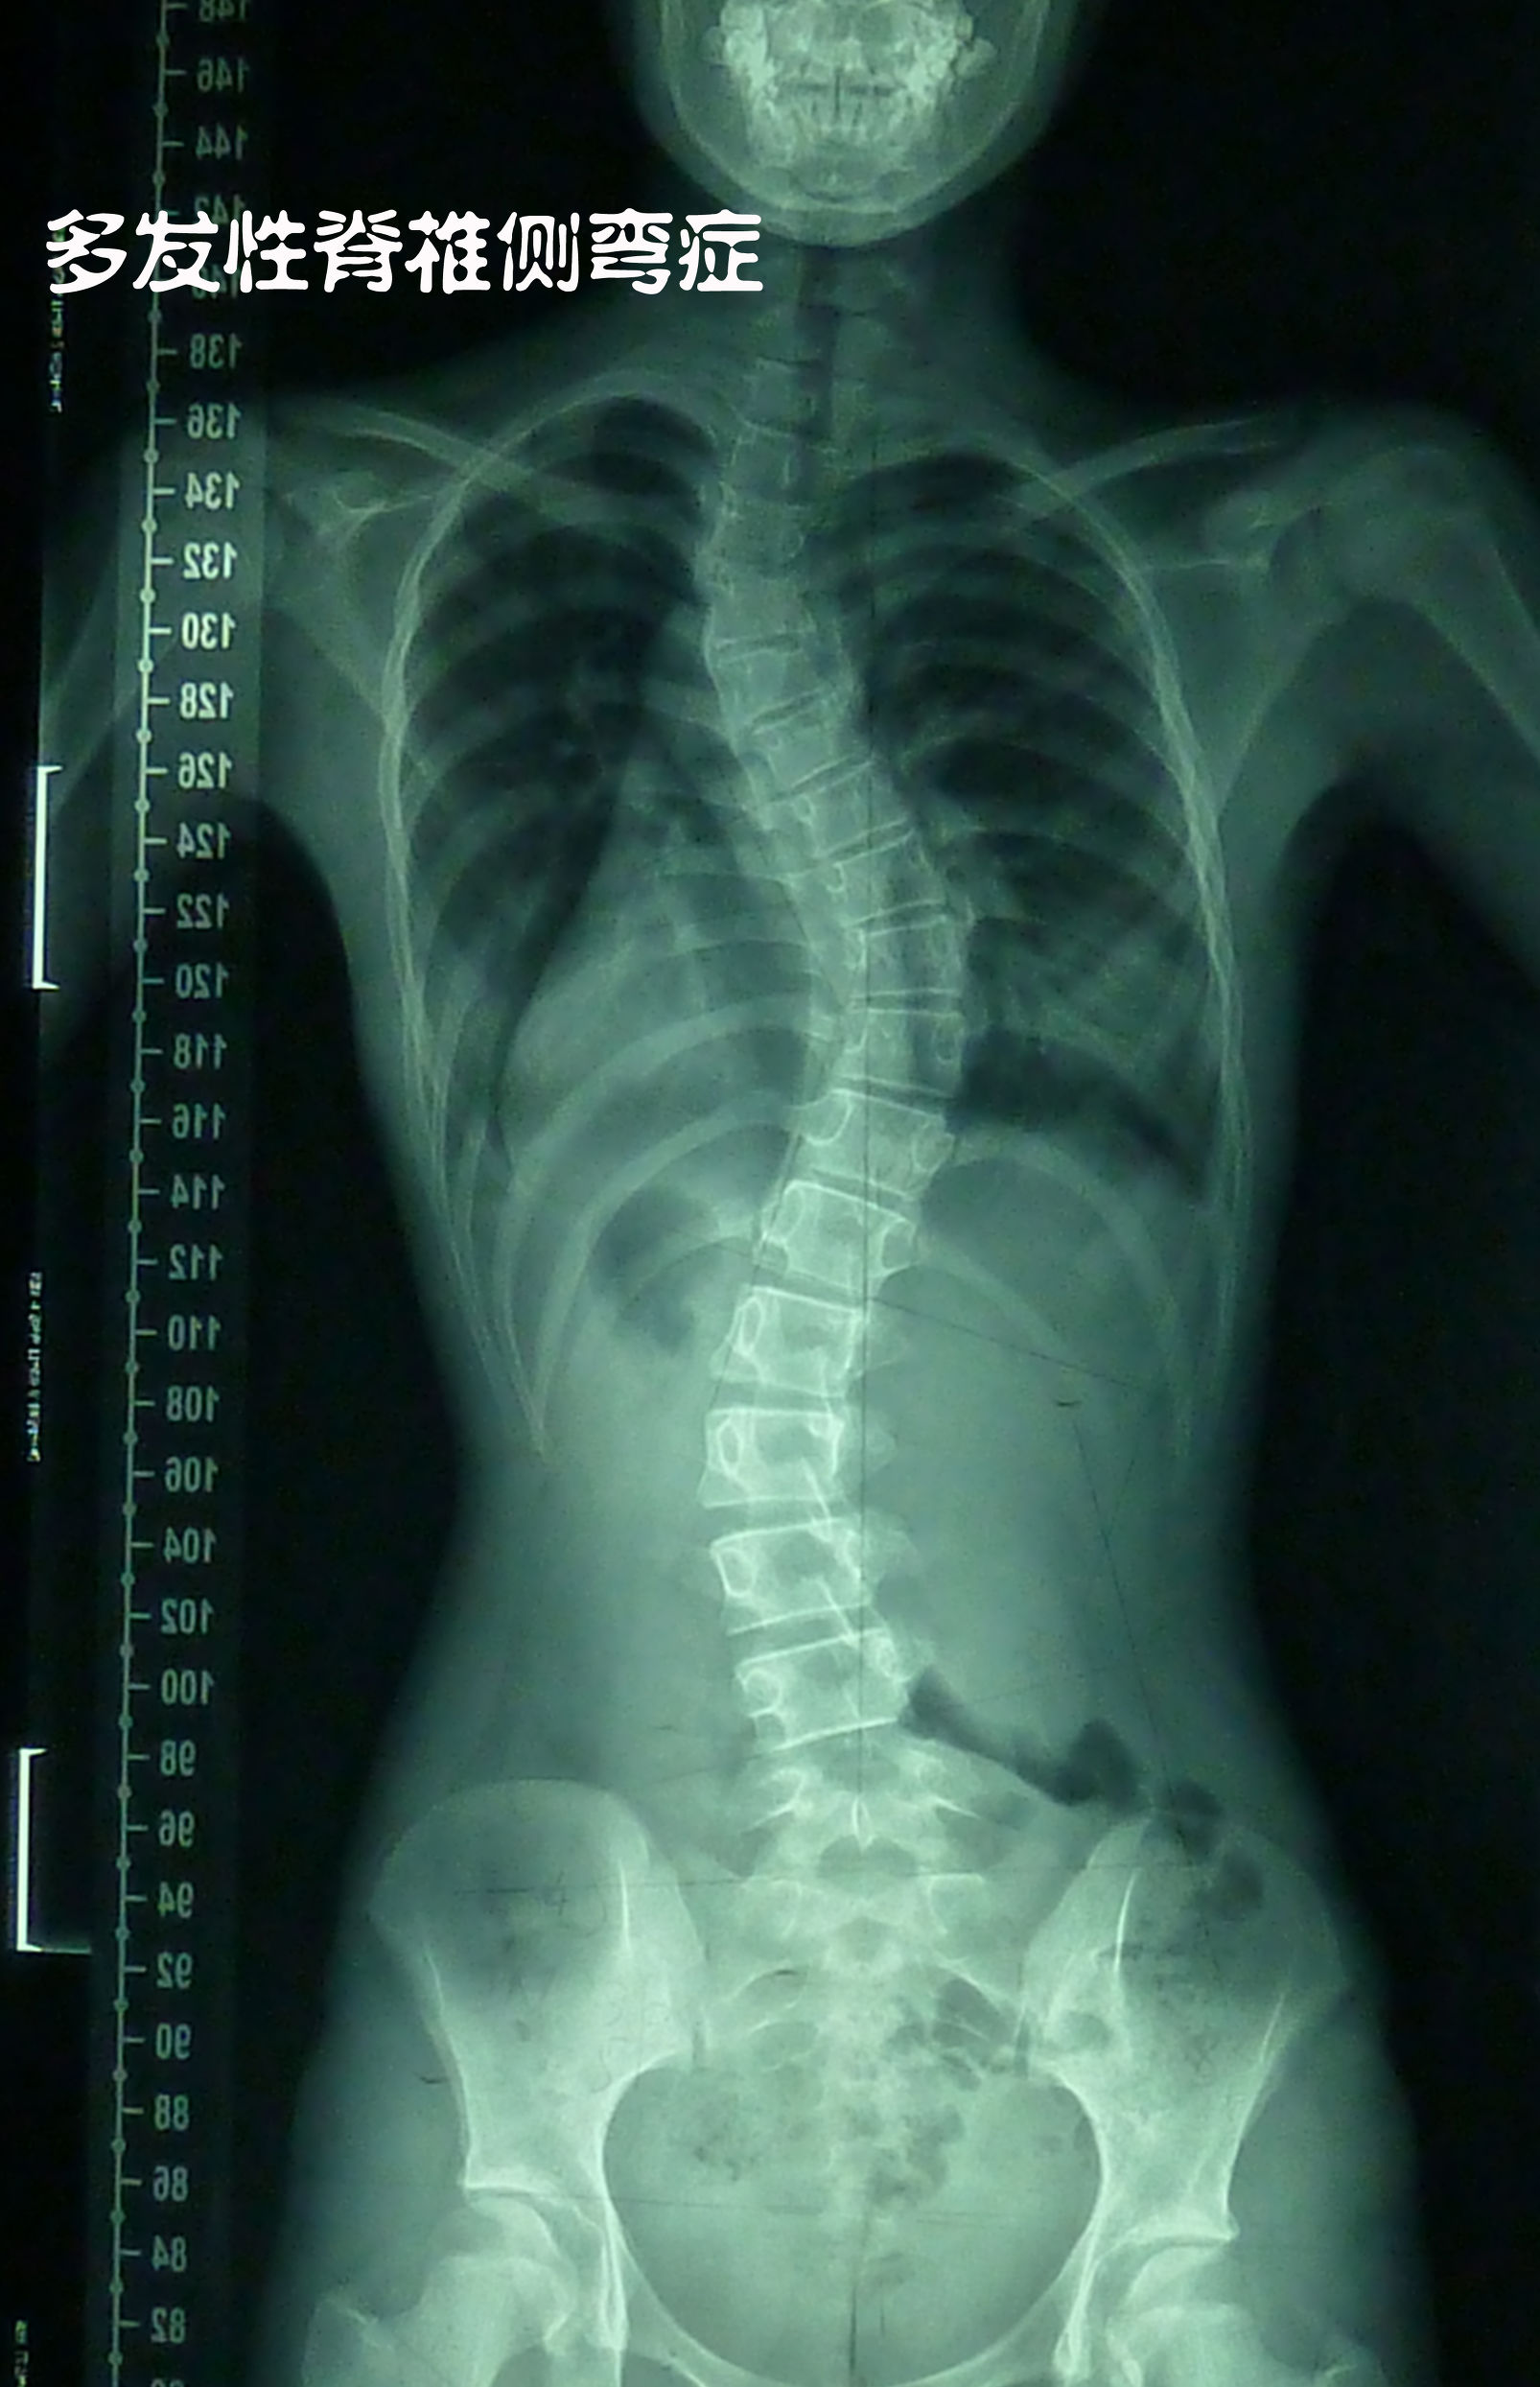

从以下图片来看,脊柱是弯曲的,而从脊柱外的轮廓(身体外形)来看,基本上是比较正常的,很难看得出身体是歪的。因为“S”型的弯曲比较对称,所以整个体型看起来就是很对称的。这个人脊柱侧弯比较厉害,还有的人弯曲没有这么大,那在外形上就更看不出来了。也正因如此,很多人活了半辈子了都不知道自己有脊柱侧弯,有得人是因为颈椎不好,或腰椎不好,去做检查才得知自己有脊柱侧弯。